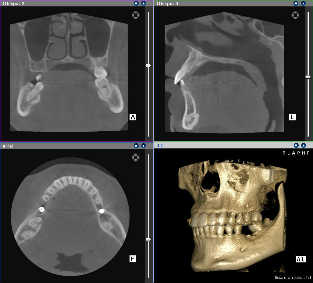

歯科用CT

CT画像

当院では歯科用CTを導入しています。CTとはコンピュータ断層撮影装置のことで、X線とコンピューターを利用することによって、体を0.1ミリ単位で輪切りにして観察することが出来ます。従来のレントゲンでは観察できなかった角度や精度で歯やあごの骨が診断できるため、より安全な治療が可能になりました。